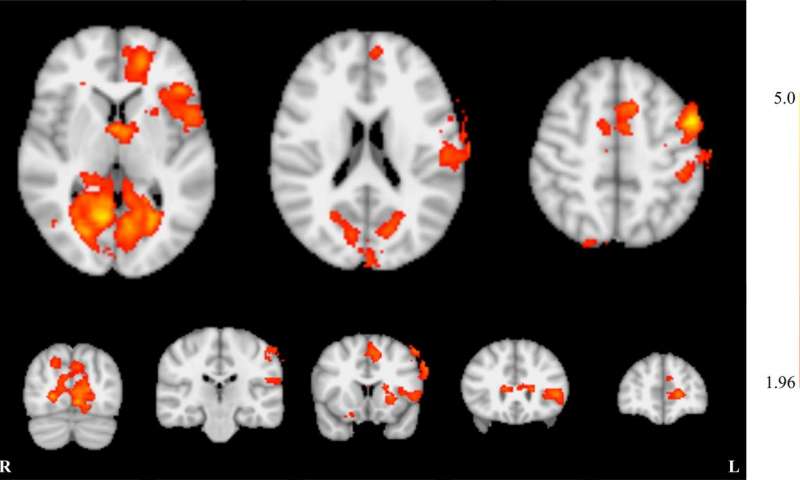

神经反馈训练的全脑效应。图片来源:北美放射学会

为了获得fMRI结果,研究人员使用单次回波平面成像,这是一种对血氧水平敏感的MRI技术,可以间接测量大脑活动。

舍伍德博士说:“我们从交替的声音和无声音开始,以便创建一个大脑地图,并找到在声音阶段产生最高活动的区域。” “然后我们选择了正在*放播**声音时激活的体素。”

然后参与者在MRI扫描仪内参与了fMRI-神经反馈训练阶段。他们通过耳塞接收白噪声,并能够将他们的初级听觉皮层中的活动视为屏幕上的条形图。每次fMRI-神经反馈训练包含8个区块,分为30秒“放松”期,然后是30秒“较低”期。指导参与者在放松期间观察酒吧,并通过在较低阶段减少初级听觉皮层活动来积极尝试降低它。